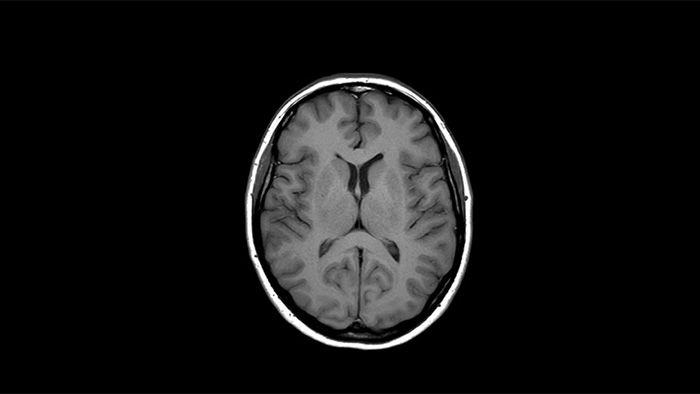

![MR Neuro Imaging]()

Damit mehr Patienten von der Magnetresonanztomographie profitieren, erfahren Sie hier mehr über neue neurologische Anwendungen von Philips Healthcare.